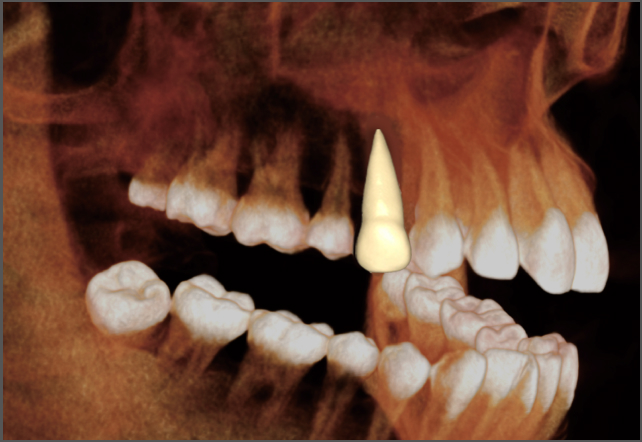

• lamtau 單顆牙齒分割

單顆牙齒分割